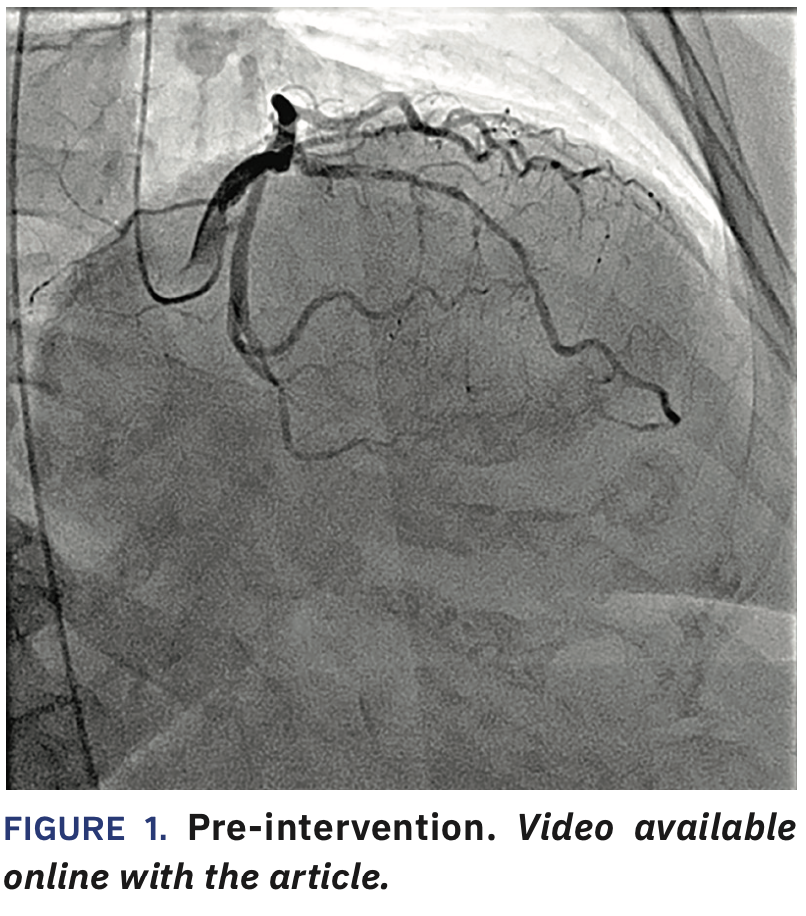

A 69-year-old obese female with history of transient ischemia attack, hyperlipidemia, hypertension, and diabetes mellitus type 2 presented with worsening anginal symptoms and dyspnea on exertion while on appropiate antianginal therapy and medical therapy, with a subsequent abnormal stress test. Her labs and echocardiogram were clinically unremarkable.

She was taken to the cardiac catheterization laboratory. Due to the small size of the patient’s radial arteries, 4 French (Fr) groin access was obtained via ultrasound with 4 Fr diagnostic catheters (Judkins Left [JL] 4, Judkins Right [R] 4) utilized to perform the diagnostic procedure (Figure 1, Video 1).

The JR4 was used to get left ventricular end diastolic pressure. The sheath was upsized to a 6 Fr size for the intervention and after giving heparin and 500 mcg nicardipine, a JL4 guide and Sion blue wire (Asahi Intecc) were used to cross the lesion. A 2.0 x 20 mm Apex balloon (Boston Scientific) was used to predilate the proximal to mid left anterior descending (LAD) coronary artery (up to 14-18 atmospheres [atm] for 7 seconds x3). 2.50 x 38 mm Synergy XD and 3.00 x 20 mm Synergy XD stents were placed (14 atm x1 and 14 atm x1), respectively in the mid and proximal vessel, followed by 2.50 x 20 mm (20 atm for 5 seconds x3) and 3.50 x 20 mm NC Apex (16 atm for 9 seconds x1) balloons. This was followed by an intravascular ultrasound (IVUS) run (Figures 2-3), resulting in further balloon dilatation with 2.75 x 15 mm (up to 16-25 atm for 7-11 seconds x4) and 3.75 x 15 mm Euphora NC (up to 18-25 atm for 7-8 seconds) (Medtronic) balloons in order to further dilate the under-expanded sections. We used CLEARstent Live (Siemens Healthineers) to help position the NC balloons. Final angiography showed a good result (Figure 4). The patient underwent closure with an Angio-Seal (Terumo) and she was placed on aspirin and ticagrelor, given the extent of stenting.

Dose area product (DAP) used in the new lab (Siemens ARTIS icono System) was 7454.21 cGycm2 versus 11740.30 cGycm2, or about 37% less compared to an older lab from a different company for a similar-sized patient and a similar intervention.*